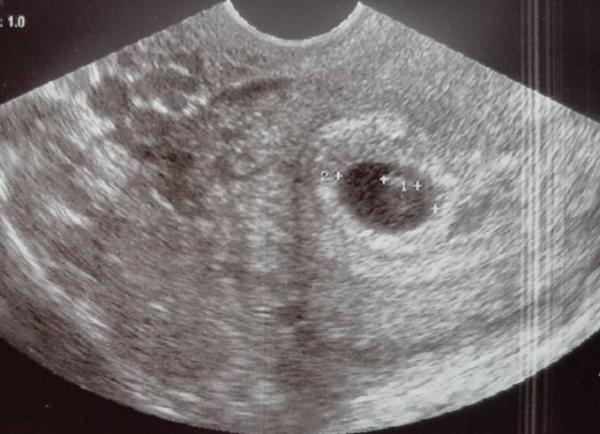

Hallo MĂ€dels Ich hatte heute bei 6+0 meinen ersten Termin. Ich habe zwar kaum Beschwerden aber eigentlich die ganze Zeit gewusst, dass alles gut ist. Aufgeregt war ich natĂŒrlich trotzdem Jedenfalls sitzt alles am richtigen Fleck und wir durften sogar das Herzchen blubbern sehen Leider ist meine Ärztin die nĂ€chsten drei Wochen im Urlaub. So lange muss ich noch im Schichtdienst ausharren. Dann habe ich auch erst den nĂ€chsten Termin. Aber ich bin positiv gestimmt. Es wird alles gut

Ja na klar :)

Bild zu

Ü Ei